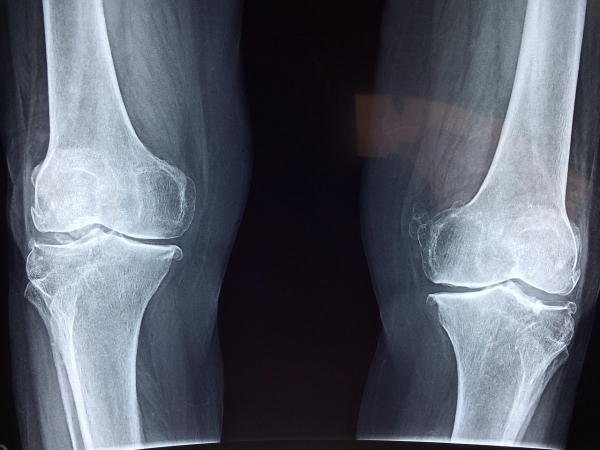

Подросток упал в траншею теплотрассы Семея и получил перелом бедра, передает Liter.kz со ссылкой на Halyqstan.

В городе идёт реконструкция тепловых сетей , однако разрытые траншеи толком не огорожены. По периметру натянута лишь сетка, которая никак не спасет от падения. Жительница Семея рассказала, что её сын-подросток, уступая дорогу проезжавшей машине, упал в эту раскопанную теплотрассу на площади Ауэзова и получил перелом бедра.

“В настоящее время мы лежим в больнице, перенесли сложную операцию. Реабилитация от одного года до двух-трех лет. Куда мне обратится? Почему ничего не загорожено? Кто будет отвечать за эти раскопки, из-за которых мой ребёнок сейчас лежит с тяжелейшими травмами в больнице?” – спрашивает мама мальчика Гульшат в одном из семейских пабликов.